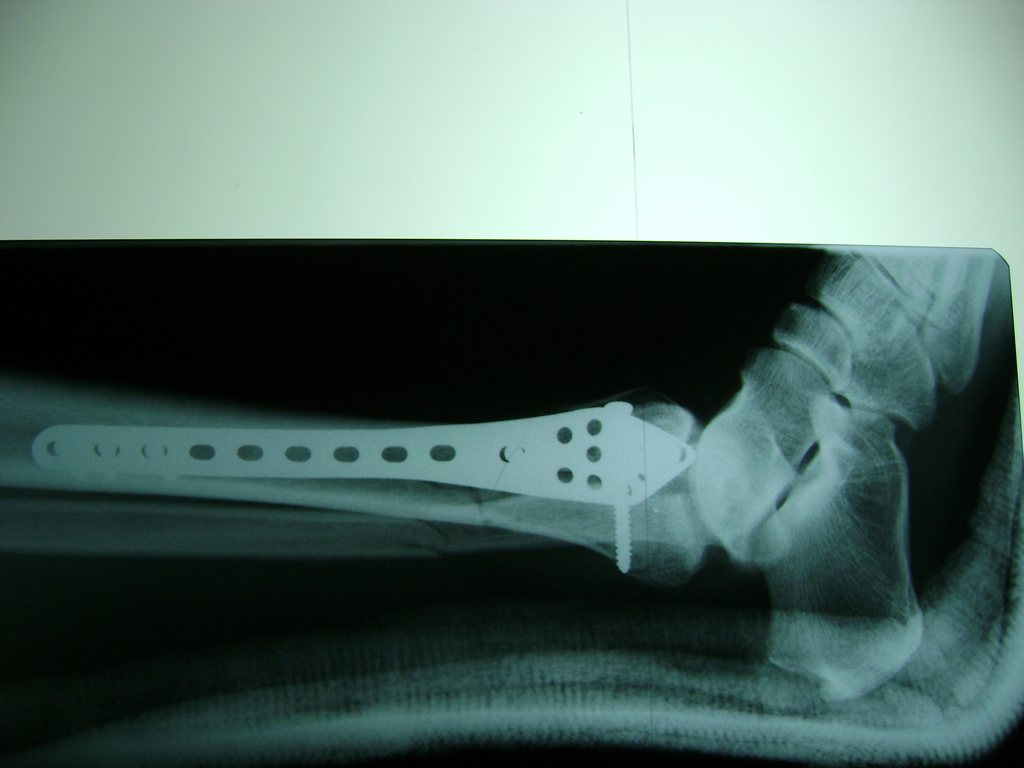

Cuando se necesita cirugía, es probable que esta implique el uso de clavijas de metal, tornillos o placas para sostener los huesos en su lugar mientras la fractura se consolida. Los elementos de soporte pueden ser temporales o permanentes.